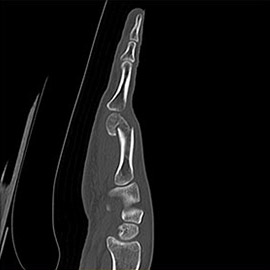

80列マルチスライスCT 検査 画像例

80列マルチスライスCTで撮影した画像

整形